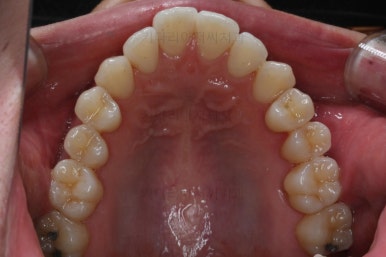

부산비수술교정 키다리아저씨치과에 처음 내원하셨을 당시의 입 안의 모습입니다.

아래 앞니에 결손치아가 하나 있네요. 송곳니-송곳니 사이에 앞니가 4개가 있어야 정상이지만 이 분은 3개에요. 의외로 아래앞니 하나 혹은 두개가 없는 경우가 굉장히 많답니다.

갯수가 맞지 않다보니 치열의 중앙도 맞지 않고 비대칭이 됩니다.

그리고 주걱턱이기 때문에 당연히 아랫니들도 앞으로 나올 수 밖에 없어 윗니보다 앞에 나와있어요.

이를 반대교합이라고 합니다.

이 분의 경우에도 전반적으로 잇몸이 약해져있을 수 밖에 없어요. 보시면 아시겠지만 잇몸 퇴축이 심해서 치아들이 길쭉길쭉해 보이죠.